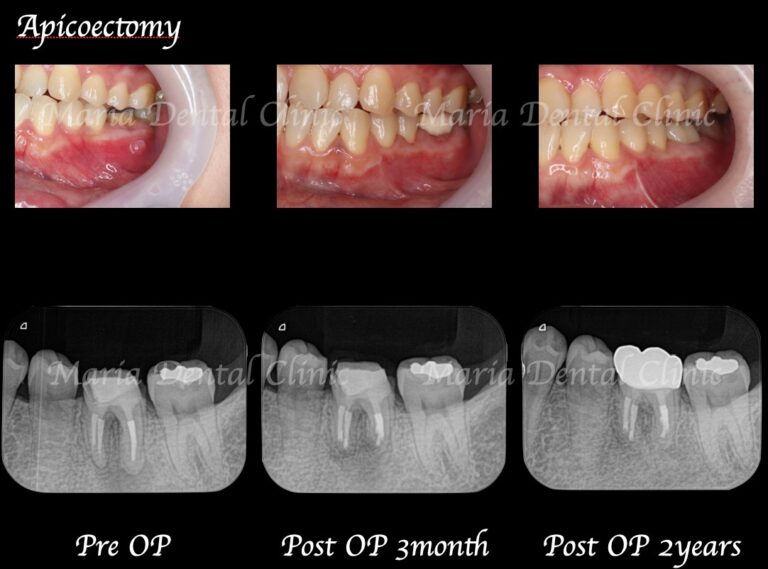

【症例】歯根端切除術により抜歯を覚悟していた歯の保存に成功

【症例】根管治療だけでは治癒に至らない歯を歯根端切除術で保存

【症例】抜歯を宣告された歯を外科的根管治療「歯根端切除術」で保存(1年後経過観察追加)